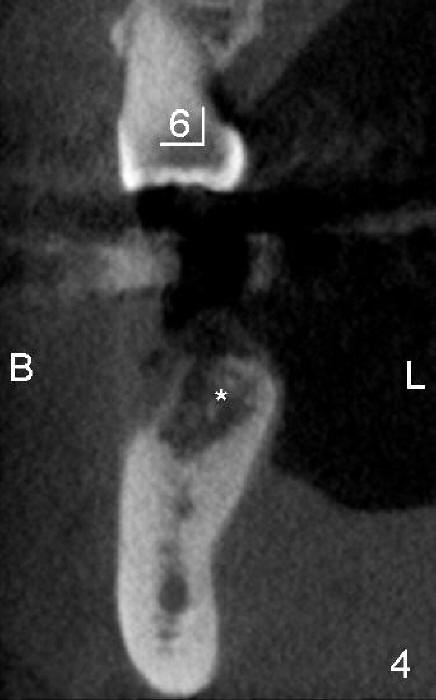

五十多岁的吴先生右下六有根分叉感染(图一),有一次到外地出差疼痛难忍拔除了,一两年后才同意植牙,图二显示已经愈合近远中(M, D)牙槽窝,六乘十七毫米植牙(图三I)好像种得很端正,其实并不完全是这样。让我们回到图二,沿着虚线做个冠状切面,显示右上六号牙以及右下六牙槽骨(图四*),与对侧六号牙冠状切面(图五)对比,右下六牙槽骨往舌侧(L)倾斜(B:颊侧),要植入长而宽的植牙,它就往舌侧倾斜(图八)。为了与对侧牙齿咬合,必须用二十度倾斜的基牙(图六A),但是临床上通过基牙而改变的角度还不够(图七),所以最后牙冠(图十C)不在植牙(I)长轴上,也就是一部分牙冠是悬臂的(*),容易造成陶瓷断裂,基牙松动。避免悬臂牙冠最好的方法便是拔牙后即刻植牙(图九),如果骨质已经吸收,植骨(图十一红色)或者骨扩张时尽量让颊侧骨板往颊侧移动,纠正植牙倾斜角度。